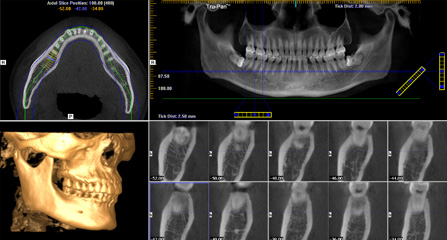

麦芽口腔着眼于全链条的数字化诊疗解决方案,与德国Kavo、瑞典Nobel、韩国奥齿泰、中国康泰健等国际知名齿科品牌合作,建立“深圳数字化口腔联盟”,应用全数字化口腔模式,从CBCT数据提取、AI口扫取模、AI智能口腔体检、数字化分析模拟与方案设计、3D打印、CAD/CAM椅旁加工以及手术模拟导航等,全流程打通数字化口腔精确诊疗的各个环节,实现麦芽数字化口腔诊疗体系新升级。

三维影像数据 一次性精确采集